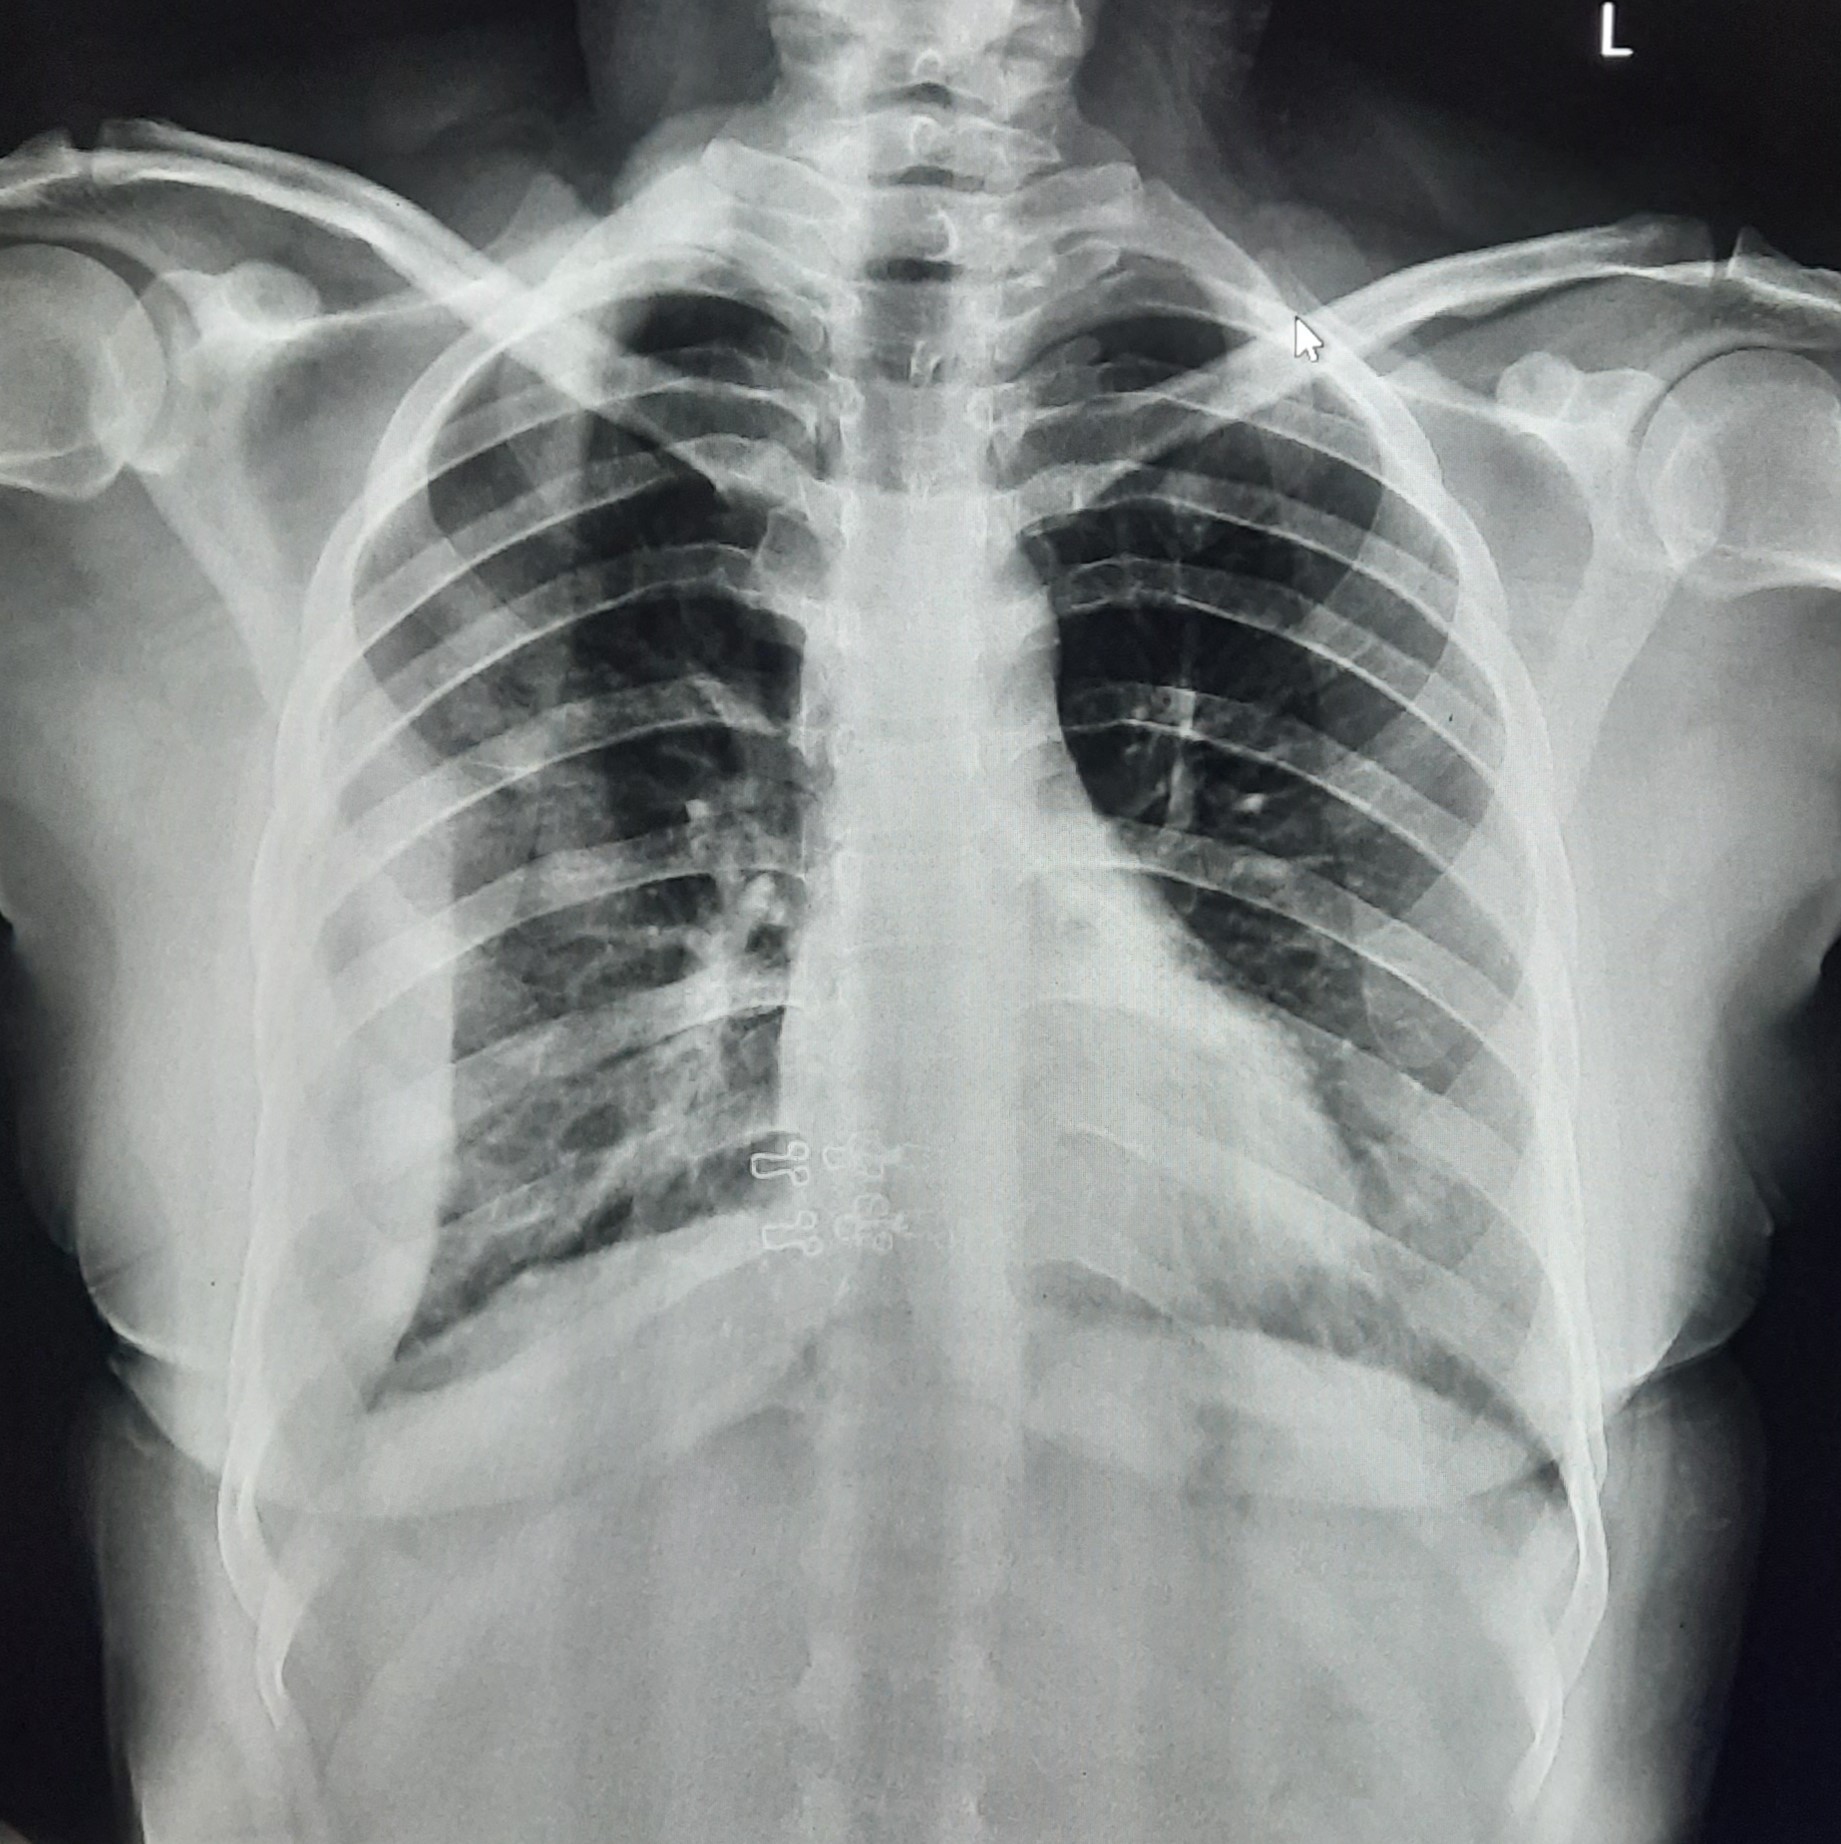

| 123 | IGGMC, Nagpur, Nagpur | P2 | 29-4349 | Dhammadip Wasnik | Consent taken on Paper | 35 Yrs. |

Provisional Diag : PTB Follow-up

Final Diag : Pulmonary Tuberculosis (Microbiologically Confirmed PTB) |

TB Case (Confirmed) | Abnormality visible on x-ray |